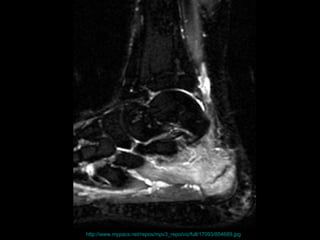

the failure of the skeleton to withstand submaximal forces over time.  the failure of the skeleton to withstand submaximal forces over time.  http://www.mypacs.net/repos/mpv3_repo/viz/full/17093/854689.jpg